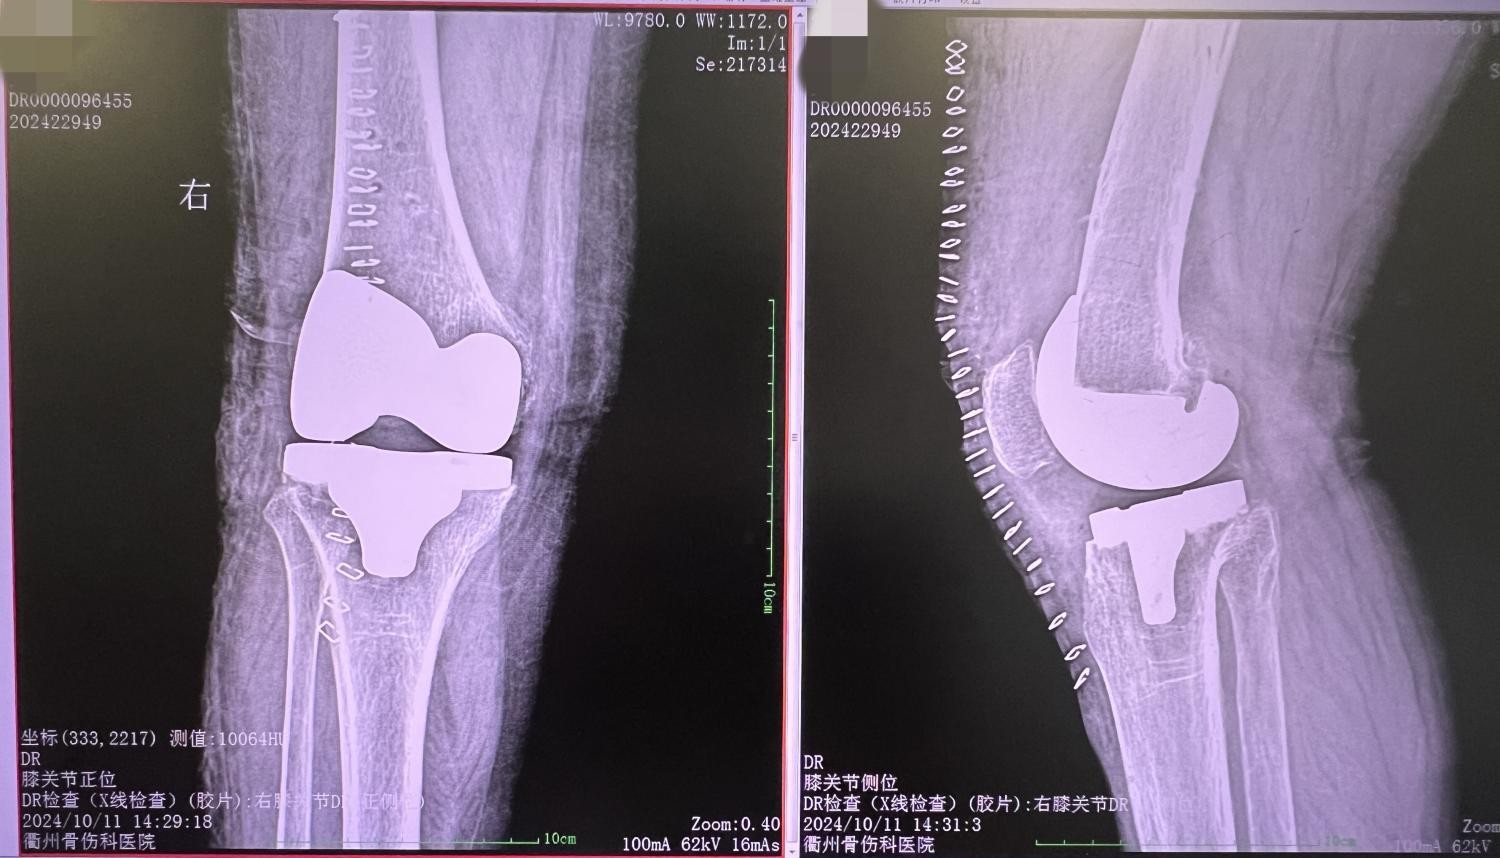

手术前

手术后

手术当天,他们小心翼翼地切开吴阿姨的膝关节部位,暴露出受损的关节。在高倍显微镜下,可以清晰地看到吴阿姨膝关节的病变情况。周主任凭借着精湛的技术和丰富的经验,仔细地清理病变组织,为接下来的关节置换做好准备。关节置换是手术的关键环节。周主任和团队成员们精确地测量患者关节的尺寸,选择合适的人工关节假体。周主任将假体准确地放置在关节部位,调整好角度和位置,确保假体与患者的骨骼完美贴合。然后,通过特殊的固定装置,将假体牢固地固定在患者的骨骼上,为患者的膝关节提供稳定的支撑。

经过一段时间的精心治疗和康复训练,吴阿姨的身体状况逐渐好转。她的双膝关节疼痛明显减轻,活动范围也逐渐增大。如今,吴阿姨已经完全愈合,准备出院。